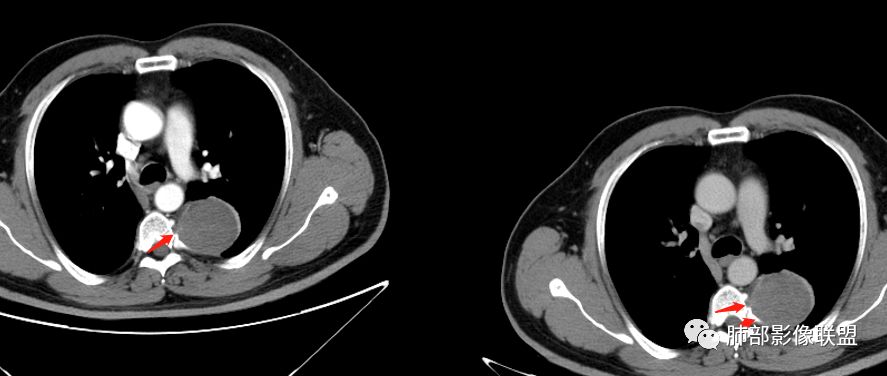

红日东升:左侧胸椎旁肿块,边缘清晰光整,冠状位见D字征,未见支气管进入,肺组织受压表现,定位肺外。轻度强化,密度稍不均匀,临近肋骨变细,未见肺动脉供血,考虑良性肿瘤,神经源性可能。右肺下叶病灶,轻度强化,血管显影,边缘平直、凹陷,考虑炎性病变。

长沟流月去无声:中年男性,慢咳起病,左后纵隔可见一大占位,D字征,胸膜掀起,有胸膜尾征,附近肺组织受挤压,血管纹理纠集,瘤肺界面清晰,较均匀轻-中度强化,瘤肺表面可见线样不张之强化影,供血血管来源不易确定,冠状位似乎见一纵隔血管出入,综合考虑神经源性肿瘤:神经纤维瘤,神经鞘瘤?右下外斑片密度影,估计炎性,但本次手术应该未处理。

ZK金:定位:左肺下叶后综合脊柱旁肺外肿块,胸膜尾征,D字征,瘤肺交界面清晰,肺组织受压。影像表现:边界清晰,密度均匀,上下经线略横经。首先考虑神经源性肿瘤,神经节细胞瘤首选,鞘瘤和孤立性纤维瘤鉴别诊断。右肺下叶考虑炎症。

M-Imaging :冠状位,还是靠近纵隔来源的

2.病灶周边见胸膜掀起,应当考虑胸壁或是纵隔来源,肺内病变不会如此。

3.降主动脉这一相对固定结构向前方推移,提示病灶相对坚实且有牢固附着点,不支持来自柔软的肺组织。

综上,病灶定位胸壁或后纵隔,就发病率而言,神经源性可能性较大。